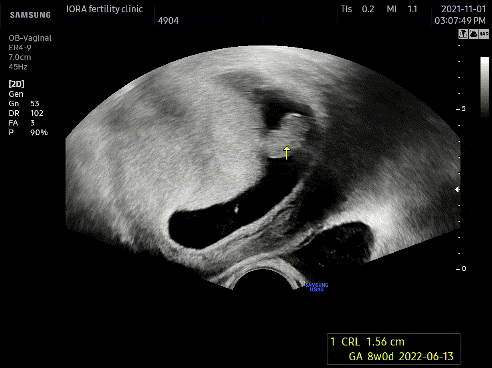

#심장음 #울롱삼 #초음파 전전주에 작은 심장음을 들었다면 7주차에는 큰 소리로 심장음을 들었다.콩알만 한데도 심장소리가 들리다니ㅠㅠ초음파를 볼 때마다 감동 아직 손발이 생기기 전이라 몸통과 머리만 있는 건장한 게 ㅎㅎ 2두신이다 귀여워 ㅎㅎ 의사선생님께서 아이는 7주차에 맞춰 잘 자라고 마음소리도 좋아서 다 좋다고 하셨다.입덧을 하며 “못 먹어도 너만 잘 컸으면 좋겠어”라고 건강에게 속삭였다. 건강하게 자라네아가ㅠㅠ!!

8주차 아이올라 방문! #초음파 몸통과 머리를 구별할 수 있는 튼튼함!흐흐흐 아 귀여워 너무 귀여워튼튼함이 잘 자라고 있구나! 훌륭하네!!점점 성장하는걸 초음파로 보면 나도 만족, 오빠도 만족. 이 순간만큼은 입덧도 감사(아이가 잘 자라고 있어서 입덧도 많이 나니까) 너만 잘 자라주면 뭐든지 좋아. 라는 생각으로 참는 것이,